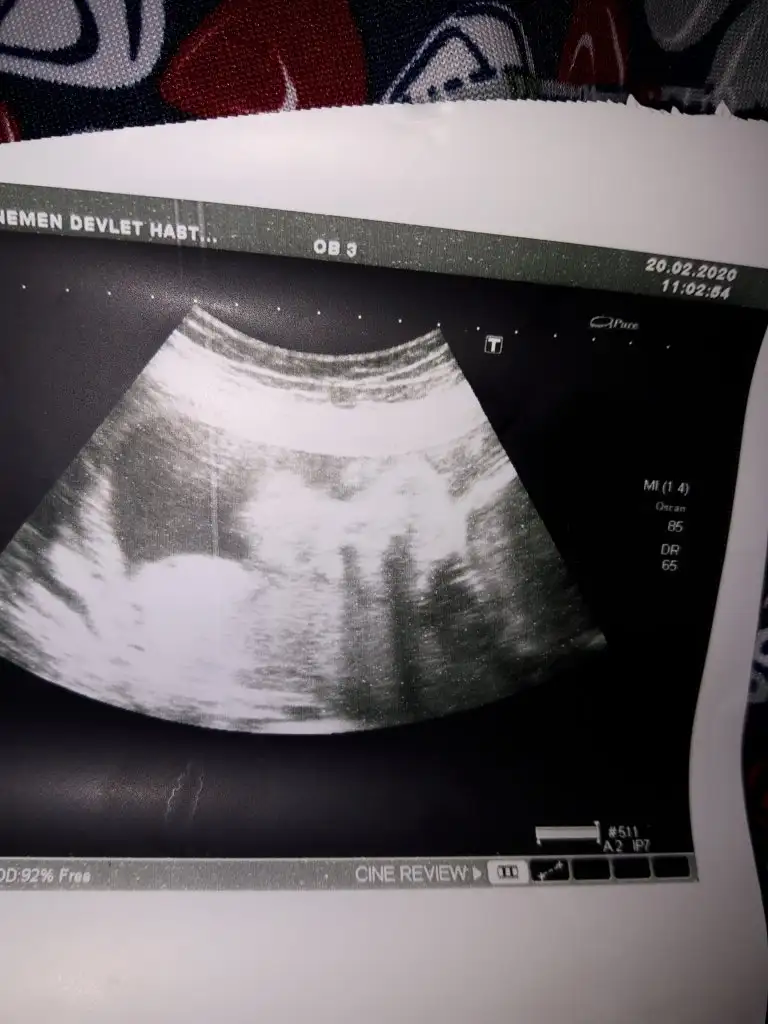

Selamlar kızlar bizim minik duruşundan cinsiyet net söylenmedi ayrıntılıya girdim soramadım söylemediler 16 haftada erkek diyebilirim dedi 20 haftada kız bu dedi son bu şekildeydi çözemedi sizce benim meleğinin cinsiyeti nedir önce sağlık tabiiki meraktan bunlar hep

Eklentiler

• 20200220_155849.webp

20200220_155849.webp

39,1 KB · Görüntüleme: 240

• 20200220_143423.webp

20200220_143423.webp

29,5 KB · Görüntüleme: 230